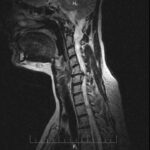

Важность МРТ шейного отдела позвоночника: диагностика, предотвращение и лечение

МРТ (магнитно-резонансная томография) шейного отдела позвоночника - это неврологическое исследование, которое позволяет получить детальные изображения структур шейного позвоночника. Этот процесс особенно важен для диагностики,...